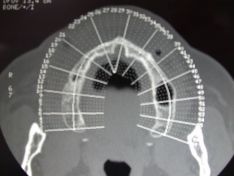

La paziente chiede, dopo tanti anni di protesi totale rimovibile, la possibilità di avere una protesi fissa. Il caso è complesso: dopo gli esami radiografici e i modelli studio viene eseguito un rialzo bilaterale dei seni mascellari. Dopo circa 8 mesi dall'intervento, sono stati posizionati gli impianti.

Rialzo del seno mascellare bilaterale e protesi totale avvitata

Rialzo del seno mascellare